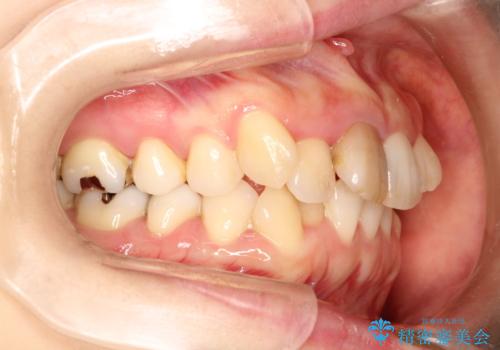

上下のガタガタのマウスピースによる非抜歯矯正

- 上下のがたつきを主訴に来院された患者様です。

上下の前歯と奥歯にがたつきがありました。

上下の奥歯を後方に移動させるのと、歯と歯の間をわずかに削ることでスペースを作り、歯を並べる計画としました。

インビザラインにて治療を行いました。

比較的がたがたの度合いが大きかったですが、しっかりとマウスピースを使用していただけたので、順調に治療を終えることができました。